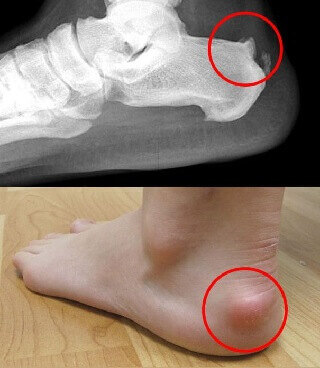

例如这样的……在门诊中,偶尔会碰到这样的病人,说自己脚后跟肿起来

偶尔会碰到这样的病人,说自己脚后跟肿起来并且伴疼痛,走路走多了

足跟后方凸起伴疼痛小心跟腱被骨头磨坏